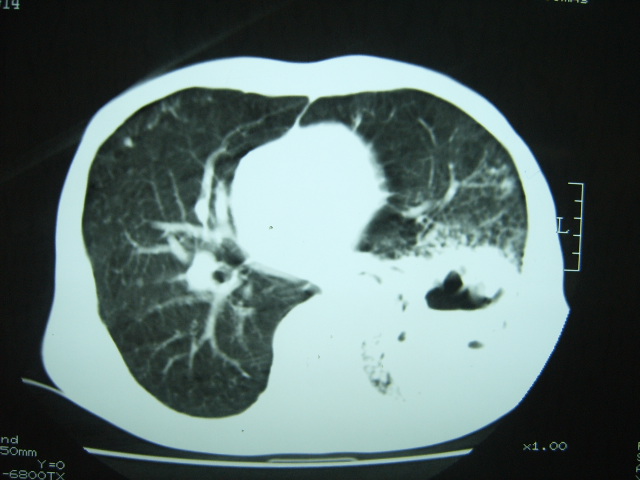

男74岁,咳嗽,寒战,低烧。有糖尿病史。

两肺结核,空洞形成,左下肺肺段隔离症待排

1、左下肺肺脓肿,合并霉菌球形成?.2、双肺陈旧性病灶.3、右上肺病灶警惕瘢痕癌,建议定期复查.

两肺结核,左下肺空洞性病变,结核性?炎性?癌性?抗炎治疗后复查。

两肺结核,左下肺大片实变,内见空洞性病变,壁不规则,结合糖尿病史,考虑:结核性?霉菌性?建议结合实验室检查或治疗后复查。